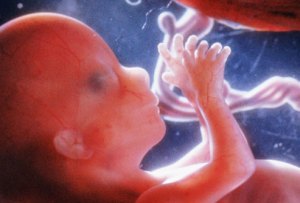

Fetus at 12 Weeks

All pictures came from:  http://www.webmd.com/baby/slideshow-fetal-development